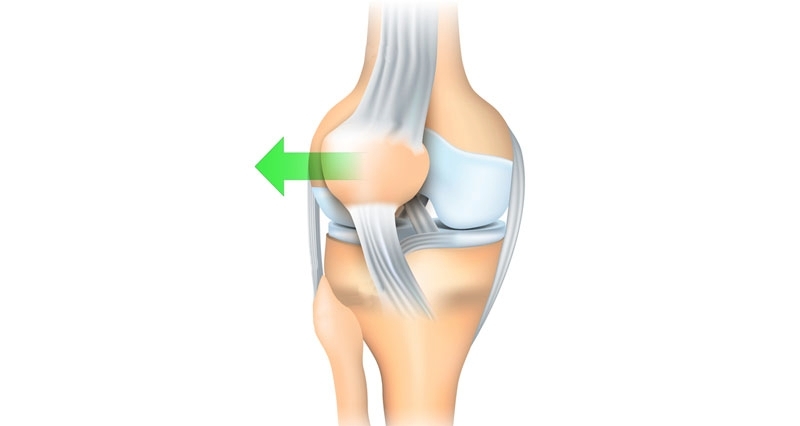

一、定義髕骨脫位是一種常見的膝關(guān)節(jié)損傷,指髕骨(膝蓋前方的類三角形骨)脫離正常的滑車溝位置,多向外側(cè)移位的情況,尤其是運動和扭轉(zhuǎn)動作中出現(xiàn),對股骨滑車和髕骨的軟骨造成重大損傷。二.常見原因1.先天性因素:股骨滑車溝較淺,高位髕骨,骨骼結(jié)構(gòu)異常、韌帶松弛等。2.外傷:運動時急轉(zhuǎn)、跳躍落地不穩(wěn)、直接撞擊膝蓋。3.肌力失衡:髕骨外側(cè)支持帶較緊,股外側(cè)肌過于強壯,股內(nèi)側(cè)肌力量減弱,導(dǎo)致髕骨被向外牽拉。4.其他:有報道認為青春期女性分泌激素會促進韌帶松弛,反復(fù)膝關(guān)節(jié)應(yīng)力負荷(如舞蹈、足球等運動)。三.典型癥狀1.急性脫位:膝蓋突然劇痛、腫脹(關(guān)節(jié)積血)。髕骨明顯移位,患者感覺膝蓋脫位或者卡住,可能自行復(fù)位或需手法推回。2.慢性不穩(wěn):反復(fù)脫位或半脫位(髕骨未完全脫離)。上下樓梯、下蹲時膝蓋打軟、恐懼感。四.診斷方法1.詢問患者病史2.體格檢查:髕骨恐懼試驗,將髕骨向外推動,患者有恐懼感覺,感覺髕骨要從膝關(guān)節(jié)脫出來;檢查髕骨活動度、穩(wěn)定性及壓痛位置。3.影像學(xué):X光:髕骨軸位片評估髕骨的傾斜和滑車溝的深淺。MRI:觀察韌帶、軟骨等軟組織損傷,如髕骨內(nèi)側(cè)支持帶撕裂,外側(cè)滑車溝及髕骨軟骨的損傷。五.治療方式1.急性期處理:手法復(fù)位后,用支具或石膏固定膝關(guān)節(jié)2-4周。冰敷、抬高患肢,藥物緩解疼痛和腫脹。2.保守治療適合首次脫位,無髕股關(guān)節(jié)發(fā)育異常者??祻?fù)訓(xùn)練:強化股內(nèi)側(cè)?。ㄈ缰蓖忍Ц撸?、拉伸外側(cè)肌群,使用髕骨穩(wěn)定護具。3.手術(shù)治療:適用于髕骨習(xí)慣性脫位,或者髕股關(guān)節(jié)發(fā)育異常且出現(xiàn)髕骨脫位的患者。A.未成年患者手術(shù)方式外側(cè)支持帶的減壓,內(nèi)側(cè)支持帶的緊縮,因為患者未成年,不鉆骨道,避免損傷骨骺,影響發(fā)育,創(chuàng)傷較小,效果滿意。B.成年患者的手術(shù)方式對于脛骨結(jié)節(jié)中心點至髁間凹的距離為15-19mm,采用髕骨二聯(lián)手術(shù);大于或者等于19mm采用髕骨三聯(lián)手術(shù)。a.髕骨二聯(lián)手術(shù)因為髕骨外側(cè)支持帶緊繃,需要在關(guān)節(jié)鏡下將髕骨外側(cè)外側(cè)松解,但是單純松解松解外側(cè)支持帶還是不能達到髕骨復(fù)位的效果,還需要做內(nèi)側(cè)支持帶松重建,國外內(nèi)側(cè)支持帶的重建取全部的腓骨長肌腱,國內(nèi)予以改良,一般取腳踝外側(cè)腓骨長肌腱前半部分,對腳踝的功能基本沒有影響。b.髕骨三聯(lián)手術(shù)有少部分患者僅做髕骨二聯(lián)手術(shù)仍不能獲得良好的效果。這些患者脛骨結(jié)節(jié)明顯的外移,脛骨結(jié)節(jié)的中心距離滑車溝的垂直距離超過19mm。這些患者在做髕骨二聯(lián)手術(shù)的基礎(chǔ)上,需要根據(jù)測量的股骨滑車溝至脛骨結(jié)節(jié)中心垂直距離,將脛骨結(jié)節(jié)內(nèi)移位后固定,稱之為髕骨三聯(lián)手術(shù)。六.預(yù)防與保健大腿肌肉訓(xùn)練和協(xié)調(diào):直腿抬高訓(xùn)練,加強大腿內(nèi)側(cè)肌肉的訓(xùn)練,按摩大腿外側(cè)肌肉,避免外側(cè)肌肉的緊繃。運動防護:運動前熱身,佩戴護膝,避免突然轉(zhuǎn)向動作。日常管理:控制體重,避免過度負重活動。

髕骨脫位(patelladislocation)是指髕骨由于多種因素脫離正常的運動軌跡向外側(cè)脫位,是最常見的急性膝關(guān)節(jié)損傷之一,占急性膝關(guān)節(jié)損傷的3%,常見于兒童和青少年。在過去的幾十年,由于參加體育運動的人數(shù)越來越多,導(dǎo)致髕骨脫位的發(fā)病率越來越高,每100,000人中就有5.8~77.8個人患有髕骨脫位,且女性較男性的發(fā)病率更高。髕骨脫位的病因眾多,通常與骨性異常或軟組織病變有關(guān)。骨性異常1.高位髕骨(patellaalta):指由于髕韌帶長度過長(>52mm)導(dǎo)致髕骨在矢狀面的垂直高度增加,是一種先天性的異常。高位髕骨是復(fù)發(fā)性髕骨脫位的高危因素,在屈膝早期階段,髕骨進入股骨滑車溝延遲,與股骨滑車的接觸面減少,骨性穩(wěn)定作用減弱,容易發(fā)生脫位。Caton指數(shù)>1.2可協(xié)助診斷。2.低位髕骨(patellainfera):指髕骨在矢狀面的垂直高度降低,大多數(shù)為獲得性,可以由外傷導(dǎo)致,也與不恰當?shù)闹委熡嘘P(guān)。根據(jù)病因,低位髕骨可分為:先天性、創(chuàng)傷性、制動性、麻痹性和醫(yī)源性。Caton?0.6,Insall<0.8可明確診斷。3.滑車發(fā)育不良:指患者的股骨滑車沒有發(fā)育成正常的凹面的解剖形狀,而是成為平坦的甚至是凸起的形狀?;颊叩墓晒腔嚋系赘叨犬惓#诨嚱诵纬晒切酝蛊?,突出于股骨干前方皮質(zhì),導(dǎo)致髕骨不得不越過滑車近端的骨性凸起才能進入滑車,從而導(dǎo)致髕骨脫位。20世紀90年代,H.Dejour首次提出采用膝關(guān)節(jié)純側(cè)位X線片評估滑車發(fā)育不良的方法,將滑車發(fā)育不良分成4型。A型:純側(cè)位片僅有交叉征,軸位片可見滑車較正常平坦。B型:純側(cè)位片可見交叉征和突起征,軸位片可見滑車外側(cè)面凸起或平坦。C型:純側(cè)位片同時可見交叉征和雙線征,但沒有突起征。軸位片可見滑車外側(cè)面凸起,內(nèi)側(cè)面發(fā)育不良。D型:純側(cè)位片同時可見交叉征、雙線征和突起征,軸位片可見滑車外側(cè)面突起,內(nèi)側(cè)滑車發(fā)育不良,甚至形成“懸崖征”(cliffsign)。4.脛骨結(jié)節(jié)過度外偏:目前脛骨結(jié)節(jié)-股骨滑車間距(tibialtubercle-trochleargroovedistance,TT-TG)通常在膝關(guān)節(jié)伸直位進行CT掃描測量,第一個掃描層面通常為通過股骨滑車關(guān)節(jié)軟骨的首個掃描平面,第二個層面通過脛骨結(jié)節(jié)的近端。TT-TG的正常參考值為<12mm,TT-TG>20mm的患者,可在MPFL重建術(shù)的基礎(chǔ)上聯(lián)合脛骨結(jié)節(jié)截骨術(shù)。軟組織病變1.多韌帶松弛癥:多發(fā)關(guān)節(jié)松弛癥(generalizedlaxity)和膝關(guān)節(jié)局部松弛癥(localizedjointlaxity)是髕股關(guān)節(jié)不穩(wěn)定的常見易患因素之一。Beighton診斷標準:滿分9分,成年人≥4分,兒童?6分即可診斷多發(fā)關(guān)節(jié)松弛癥。2.髕內(nèi)側(cè)穩(wěn)定結(jié)構(gòu)損傷:內(nèi)側(cè)髕骨股骨韌帶(medialpatellofemoralligament,MPFL)是限制髕骨外移的一級穩(wěn)定結(jié)構(gòu),是髕骨穩(wěn)定的最重要的軟組織穩(wěn)定結(jié)構(gòu)。MPFL斷裂后不僅會導(dǎo)致髕骨外移的顯著增加,同時還將增大股骨滑車外側(cè)面的壓力,導(dǎo)致膝前痛、骨性關(guān)節(jié)炎等疾病。根據(jù)遺傳病因?qū)W,髕骨脫位可分為復(fù)發(fā)性髕骨脫位、習(xí)慣性髕骨脫位和先天性髕骨脫位。復(fù)發(fā)性髕骨脫位:復(fù)發(fā)性髕骨脫位是由于急性髕骨脫位發(fā)展而來,常常伴隨內(nèi)側(cè)髕骨股骨韌帶損傷,并可能伴有髕骨內(nèi)側(cè)關(guān)節(jié)軟骨或股骨外髁骨軟骨骨折,通??勺孕袕?fù)位。多數(shù)患者自訴在受傷時有“髕骨錯位感”,臨床檢查可發(fā)現(xiàn)膝關(guān)節(jié)內(nèi)側(cè)支持帶區(qū)域壓痛、膝關(guān)節(jié)內(nèi)側(cè)血腫以及髕骨外推恐懼試驗陽性。習(xí)慣性髕骨脫位:習(xí)慣性髕骨脫位又稱隨意性髕骨脫位。表現(xiàn)為每次屈膝時均發(fā)生髕骨脫位,完全伸膝時復(fù)位,患者通常沒有疼痛主訴。其發(fā)病機制是由于股四頭肌的短縮,因此若手法強行限制髕骨脫位,膝關(guān)節(jié)的屈曲會受限。在習(xí)慣性髕骨脫位的患者中,常合并膝外翻(valgus)、股骨滑車發(fā)育不良(trochleardysplasia)、伸膝裝置短縮、脛骨結(jié)節(jié)外偏(tibialtuberclelateralization)、股骨和脛骨扭轉(zhuǎn)畸形(femoralandtibialtorsionaldeformity)等。固定性髕骨脫位:固定性髕骨脫位包括先天性髕骨脫位以及由外傷導(dǎo)致的急性髕骨脫位發(fā)展而來。前者是出生時即出現(xiàn)的髕骨脫位(通常在10歲以前發(fā)現(xiàn));后者是因外傷導(dǎo)致髕內(nèi)側(cè)穩(wěn)定結(jié)構(gòu)完全失去穩(wěn)定功能。固定性髕骨脫位的患者,無論膝關(guān)節(jié)是伸直還是屈曲,髕骨始終處于脫位狀態(tài)且不能復(fù)位。與習(xí)慣性髕骨脫位相比,復(fù)發(fā)性髕骨脫位的患者往往有明顯的外傷史,習(xí)慣性髕骨脫位的患者可能伴隨先天性的骨性異常以及軟組織病變。復(fù)發(fā)性髕骨脫位可通過保守治療恢復(fù)髕骨穩(wěn)定性,但二次損傷可能導(dǎo)致髕骨再次脫位,每次均可通過手法復(fù)位;而習(xí)慣性髕骨脫位可在每次屈膝時出現(xiàn),僅在完全伸膝時可復(fù)位,強行手法復(fù)位可能會導(dǎo)致膝關(guān)節(jié)活動受限。因此在臨床診斷時,需詳細詢問病人的病史,并結(jié)合查體謹慎辨別兩種髕骨脫位。髕骨脫位的治療方案可分為保守治療和手術(shù)治療。對于初發(fā)的急性髕骨脫位,可采取保守治療?;颊咄ㄟ^3周的鉸鏈式伸直位支具固定,配合理療和藥物治療可緩解腫脹和疼痛,3周后可在專業(yè)康復(fù)師的指導(dǎo)下進行康復(fù)訓(xùn)練:ROM訓(xùn)練恢復(fù)關(guān)節(jié)活動度、VMO強化訓(xùn)練和核心肌群訓(xùn)練增強髕骨穩(wěn)定性以及髂脛束拉伸訓(xùn)練減少髕骨外側(cè)牽拉力。6周后門診復(fù)查,若保守治療無效,無法維持復(fù)位或反復(fù)脫位者則建議手術(shù)治療。手術(shù)治療要根據(jù)患者存在的主要病理因素設(shè)計手術(shù)方案,即使是同一種脫位類型,在不同患者可能會接受不同的手術(shù)方案。手術(shù)方案包括兩大類。一是近端力線矯正術(shù),二是遠端力線矯正術(shù)。近端力線矯正術(shù)包括:股骨遠端截骨術(shù)、滑車成形術(shù)、外側(cè)支持帶松解或延長術(shù)以及MPFL重建術(shù)等;遠端力線矯正術(shù)包括脛骨結(jié)節(jié)截骨術(shù)、髕腱外側(cè)半內(nèi)移術(shù)、脛骨近端截骨術(shù)等。多數(shù)髕骨脫位患者需要接受MPFL重建術(shù)。可選擇不同的移植物代替原本的MPFL,自體移植物包括自體半腱肌腱、股薄肌腱、內(nèi)收肌腱、股四頭肌腱、髕韌帶、髂脛束及闊筋膜等,異體移植物包括異體骨-髕腱復(fù)合體、異體脛前肌腱或半腱肌腱等,或人工韌帶。臨床多選用自體半腱肌腱作為移植物。髕骨脫位是臨床青少年人群較為常見的膝關(guān)節(jié)疾病,明確其分型對于治療方案的選擇和治療效果至關(guān)重要。在手術(shù)治療前要認真、個體化地分析導(dǎo)致患者髕骨脫位的病理因素。手術(shù)治療要圍繞引起患者髕骨脫位的主要病理因素設(shè)計手術(shù)方案,同一類型的髕骨脫位也可能通過不同術(shù)式解決。